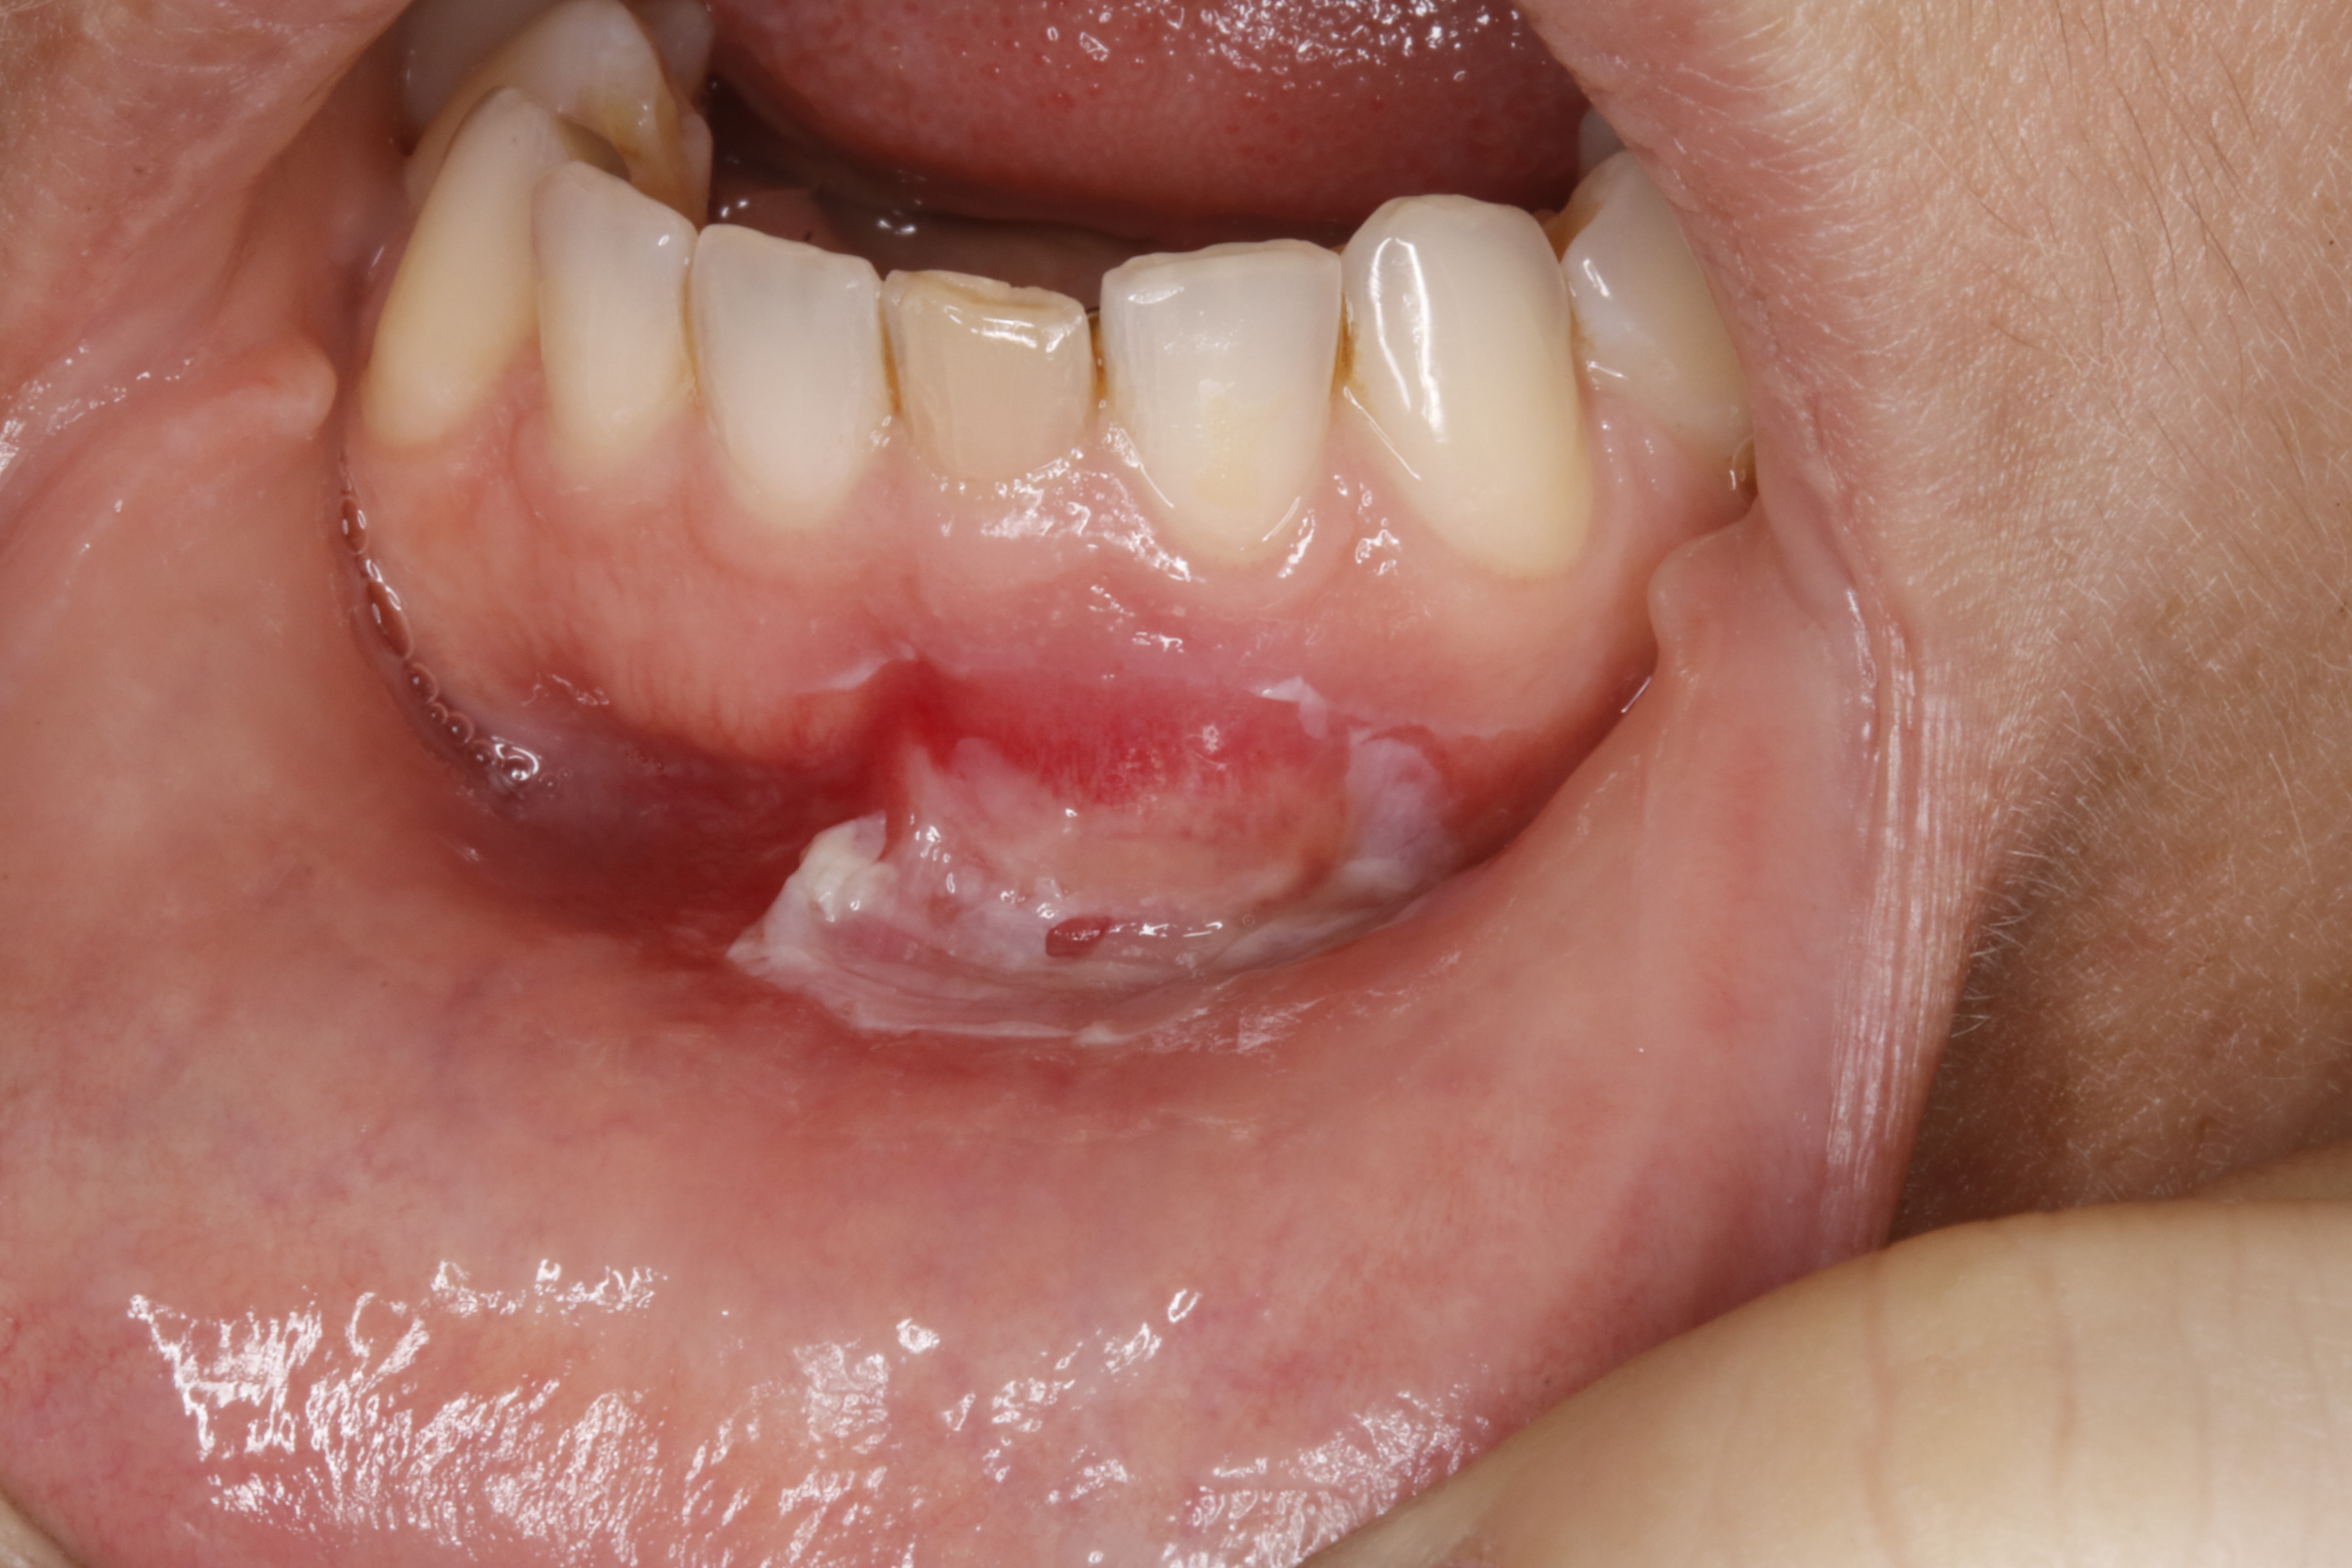

bonjour , j essaye de comprendre le pourquoi de cette reaction si importante et si rapide :

- acte 1 la dent est necrosée , asymptomatique , et lors d un contrôle det , une radio est prise . suite à une image à l apex , l' endo est faite , . , sans anesthesie . ok .

- acte 2 une petite boule blanche est apparue le lendemain , soit

- acte 3 du coup 2 jours apres , une anesthésie a eté faite autour de la boule fistulisante , et avec des compresses , la boule a eté crevée et esquichéé en appuyant bien fort pour bien faire tout sortir . ( !? )

1/ l aspect que ça a

je pense à une brulure au paroex pour l aspect blanc filandreux , et probablement à un double canal resté vivant pour ce qui est de la douleur au froid .

et puis probablement qu en esquichant la pression du pus a du décoller les plans muquex .

j ai passé un p'tit coup de fil a sa mere ce matin , il parait que ç est encore plus blanc malgré l arrêt du paroex depuis vendredi .

Ça ressemble effectivement à une lésion ischémique.

A voir aussi si le périoste a pas été ramoné par l'aiguille durant l'anesthésie.

Parfois chez un patient qui si prête tu peux éplucher l'épithélium, il faut muqueuse sèche, ta compresse ou ton coton va "coller" et enlever la couche superficielle, après sa ressemble à ton truc sur la zone "décollée", c'est douloureux et guérit lentement mais surement.

Concernant une éventuelle ischémie c'est louche car concerne surtout la muqueuse de la lèvre.... Et pas tellement la gencive attachée.

C'est quoi a droite en bouche ? Un hématome ?

Ça fait plus penser à une brûlure ou une réaction à un produit irritant ou à un peeling comme décrit par vulpi... Ou les trois...